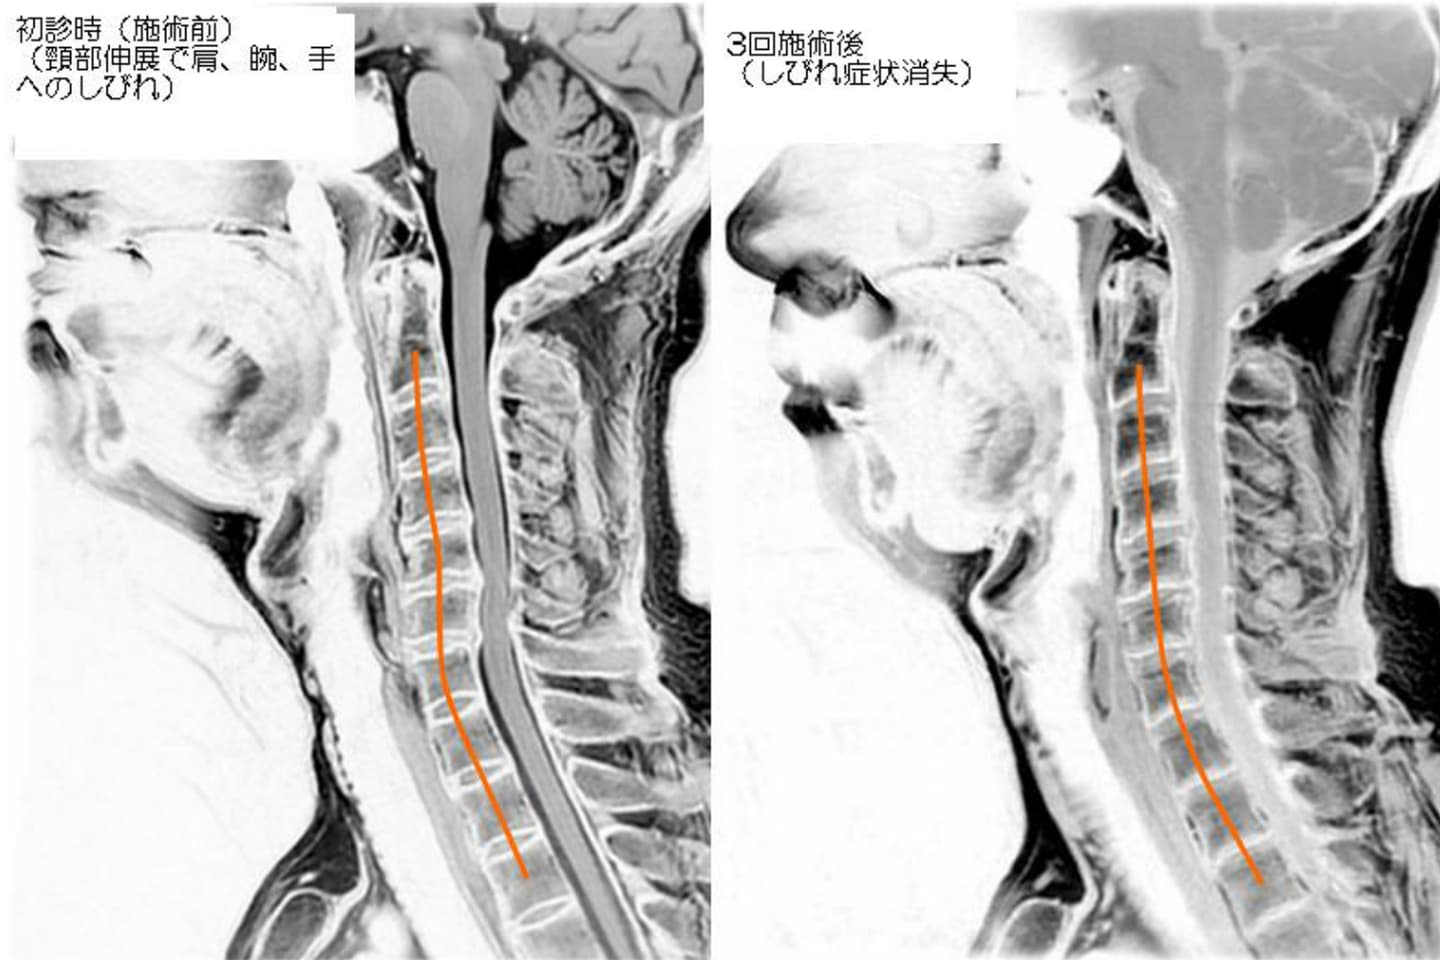

ふたば整体院では病院でのレントゲン検査や

MRI検査をお願いすることあります。

それはより正確に原因を特定し、より安全に

施術をするため。

そしてフィルムやCD-ROMで持ってきて頂いた

画像をもとに、カイロプラクティック独自の

解析をしていきます。

実際に触れて、動かしての検査と画像で得られた

情報を照らし合わせ、より効果的な施術を提供

できるようにしています。